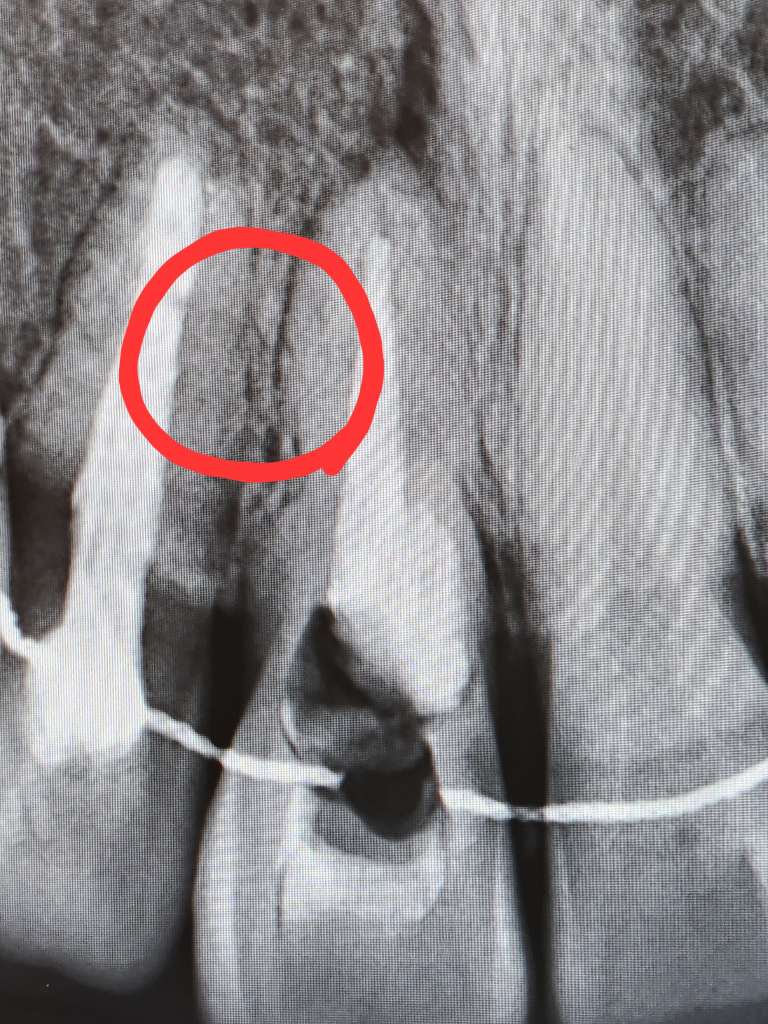

상담해주실때, 지금 이정도로 뚫어서 진행을 했었고, 아직도 안쪽에 사진상 보이는 저 검은색 부분이 오염된 부분이며 치아 안쪽을 더 뚫어서 다 제거하기에는 치아 외벽이 거의 남아있지 않아 치아 자체가 부서질 수 있다고 하셨습니다.

치아 내부에 약을 넣었는데 잇몸으로 약이 흘러나온다는 건

치아에 이미 균열이 있다는 뜻이고,

또 그렇다면 내부에 남아있는 충치균이

그 균열된 부분을 통해서 나온다거나,

아니면 나오진 않더라도 내부에 오염된 채 있으면

치아 내부에서 계속 썩어들어가는것이 아닐지

였습니다.

이 부분에 대해서는 균열이 있을 수도 있으나 그럴일은 없다 라는 식으로...? 말씀을 뭐라 해주셨었는데 제입장에선 이해가 잘되지 않았어서 정확히 기억이 나지 않습니다.

치아 뿌리끝에도 염증이 잇는거 같습니다. 소견서를 받아서 대학병원 보존과를 가셔서 검진을 받아보시는게 좋을것같습니다.